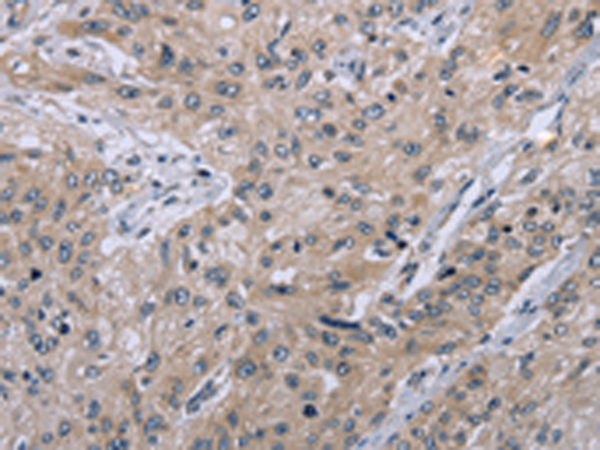

分类: 科研抗体货号: P08269别名: CRI1; EID-1; RBP21; PTD014; C15orf3; PNAS-22; IRO45620应用: IHC反应种属: Human